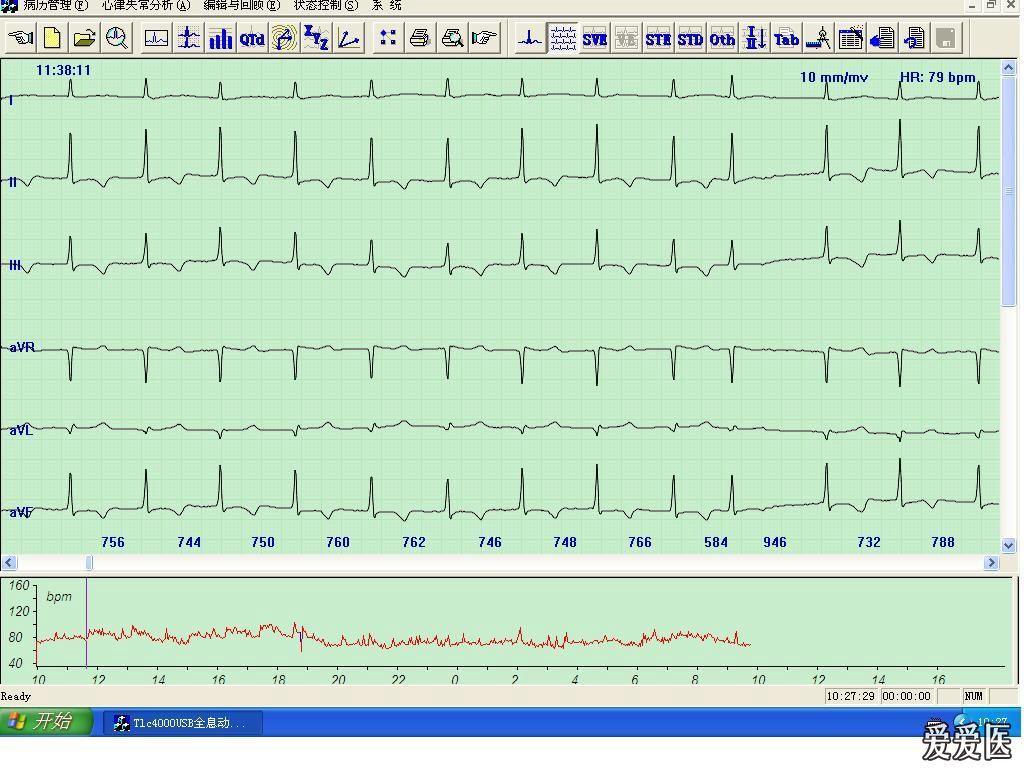

24小时动态心电图检查(Holter心电图)的优势和注意事项24小时动态心电图又称Holter心电图,是通过受检者随身佩带的心电图记录器,应用数据磁带记录装置,可连续记录24~48小时体表心电图,有的记录仪可间断记录72小时甚至更长时间,然后利用回放系统经电子计算机处理作快速阅读和分析,不仅可分别显示监测期内心搏总数最快心率、最慢...

24小时动态心电图(Holter)的优势和检查时的注意事项心脏跳动的全程监测 动态心电图又称 Holter心电图,是通过受检者随身佩带 的心电图记录器,应用数据磁带记录装置,可连续记录24-48小时体表心电图,有的记录仪可间断记录72小时甚至更长时间,然后利用回放系统经电子计算机处理作快速阅读和分析,不仅可分别显示监测期内心搏总数、...

∪0∪ 24小时动态心电图的适应症动态心电图是通过动态心电图仪在患者日常生活状态下连续24小时或更长时间记录其心电活动的全过程,并借助计算机进行分析处理,以发现在常规体表心电图检查时不易发现的心律失常和心肌缺血等,为临床诊断、治疗及判断疗效提供重要的客观依据。动态心电图仪由美国Holter1949年...